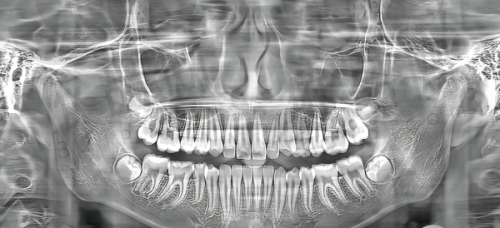

该口腔机构配备了必要的牙科设备,这些设备对于种植牙手术的成功至关重要。治疗椅操作灵活,可以调节角度,能够让患者在治疗过程中保持舒适的姿势。影像设备如口腔 CT 等,能拍摄牙齿的详细情况,帮助医生全方面了解患者的口腔状况,制定更加精细的治疗方案。此外,消毒设备严格执行操作规范,确保治疗过程的卫生和安心,避免交叉感染。